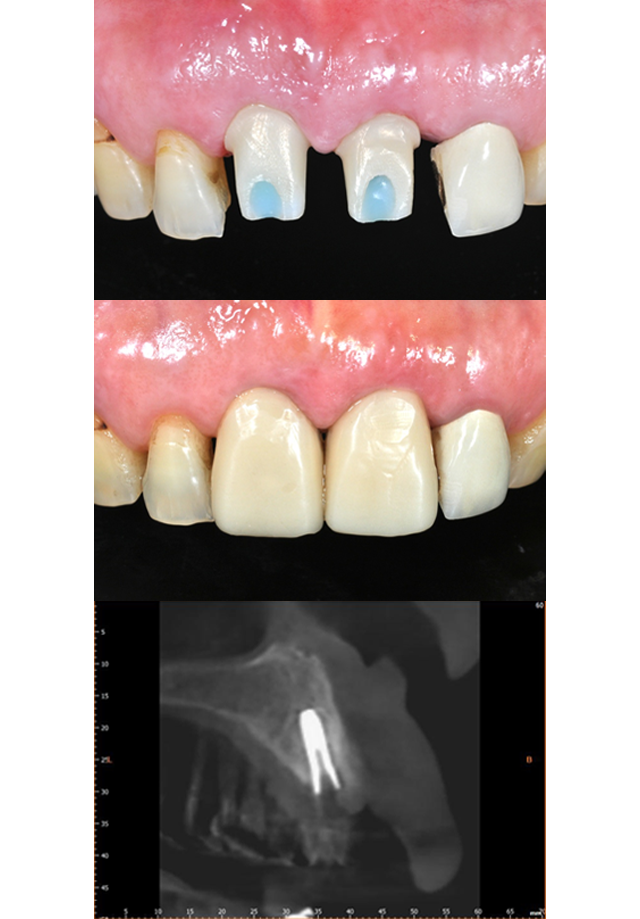

임플란트 시술과 보철물 체결이 원데이로 이루어진 케이스 입니다.

식립오차 감소

골푹이 좁고 식립각도가 중요한 앞니 임플란트의 식립오차를 줄여줌